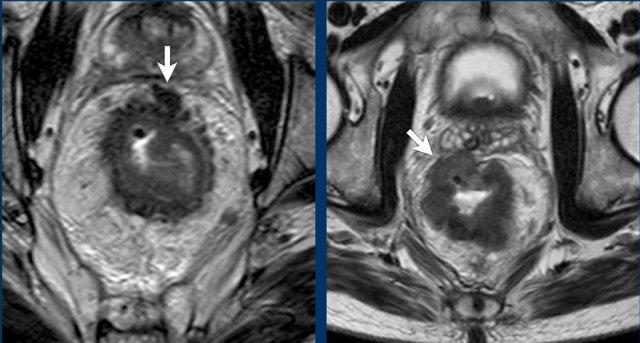

Hình ảnh

- Hình ảnh bên trái: Hạch bạch huyết bệnh lý 9 mm ở khoang bịt bên trái (mũi tên), được xác định tại thời điểm phân loại giai đoạn ban đầu. Cần xạ trị và/hoặc cắt bỏ riêng biệt để tránh tái phát bên ngoài.

- Hình ảnh bên phải: Bệnh nhân được điều trị bằng phương pháp TME tiêu chuẩn (không cắt hạch bên) đã xuất hiện khối u không đều ở khoang bịt trái, phù hợp với tái phát hạch bên.

Ví dụ về một bệnh nhân có nhiều hạch cN+ phì đại không đều tại thời điểm phân giai đoạn ban đầu. Sau hóa xạ trị, hầu hết các hạch đã biến mất và chỉ còn lại một hạch nhỏ < 5 mm, gợi ý giai đoạn ycN0.